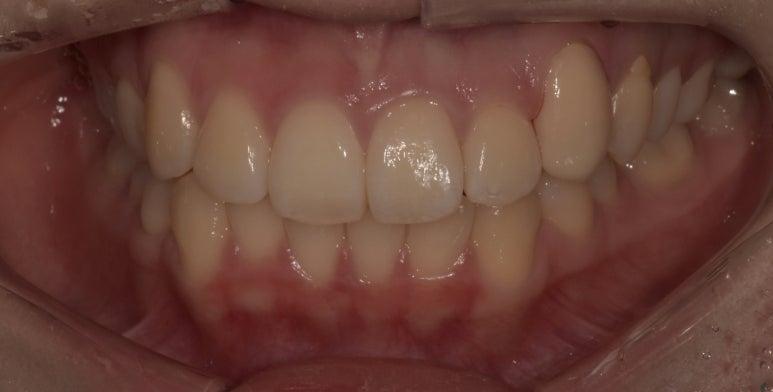

덧니라미네이트 시술 전후

(전) 20241-01-17 (후) 2024-01-24

치료를 마친 모습을 전과 비교해보니 어떤가요?

잇몸라인이 다소 올라가 있는 부분은 어쩔 수 없지만, 앞으로 툭 튀어나와있던 치아가

다른 치아와 유사한 라인으로 맞춰져 더 가지런해 보이죠?

보시면 라미네이트 한 치아와 다른 치아의 색상 또한 큰 차이가 없는 것이 느껴지시죠?